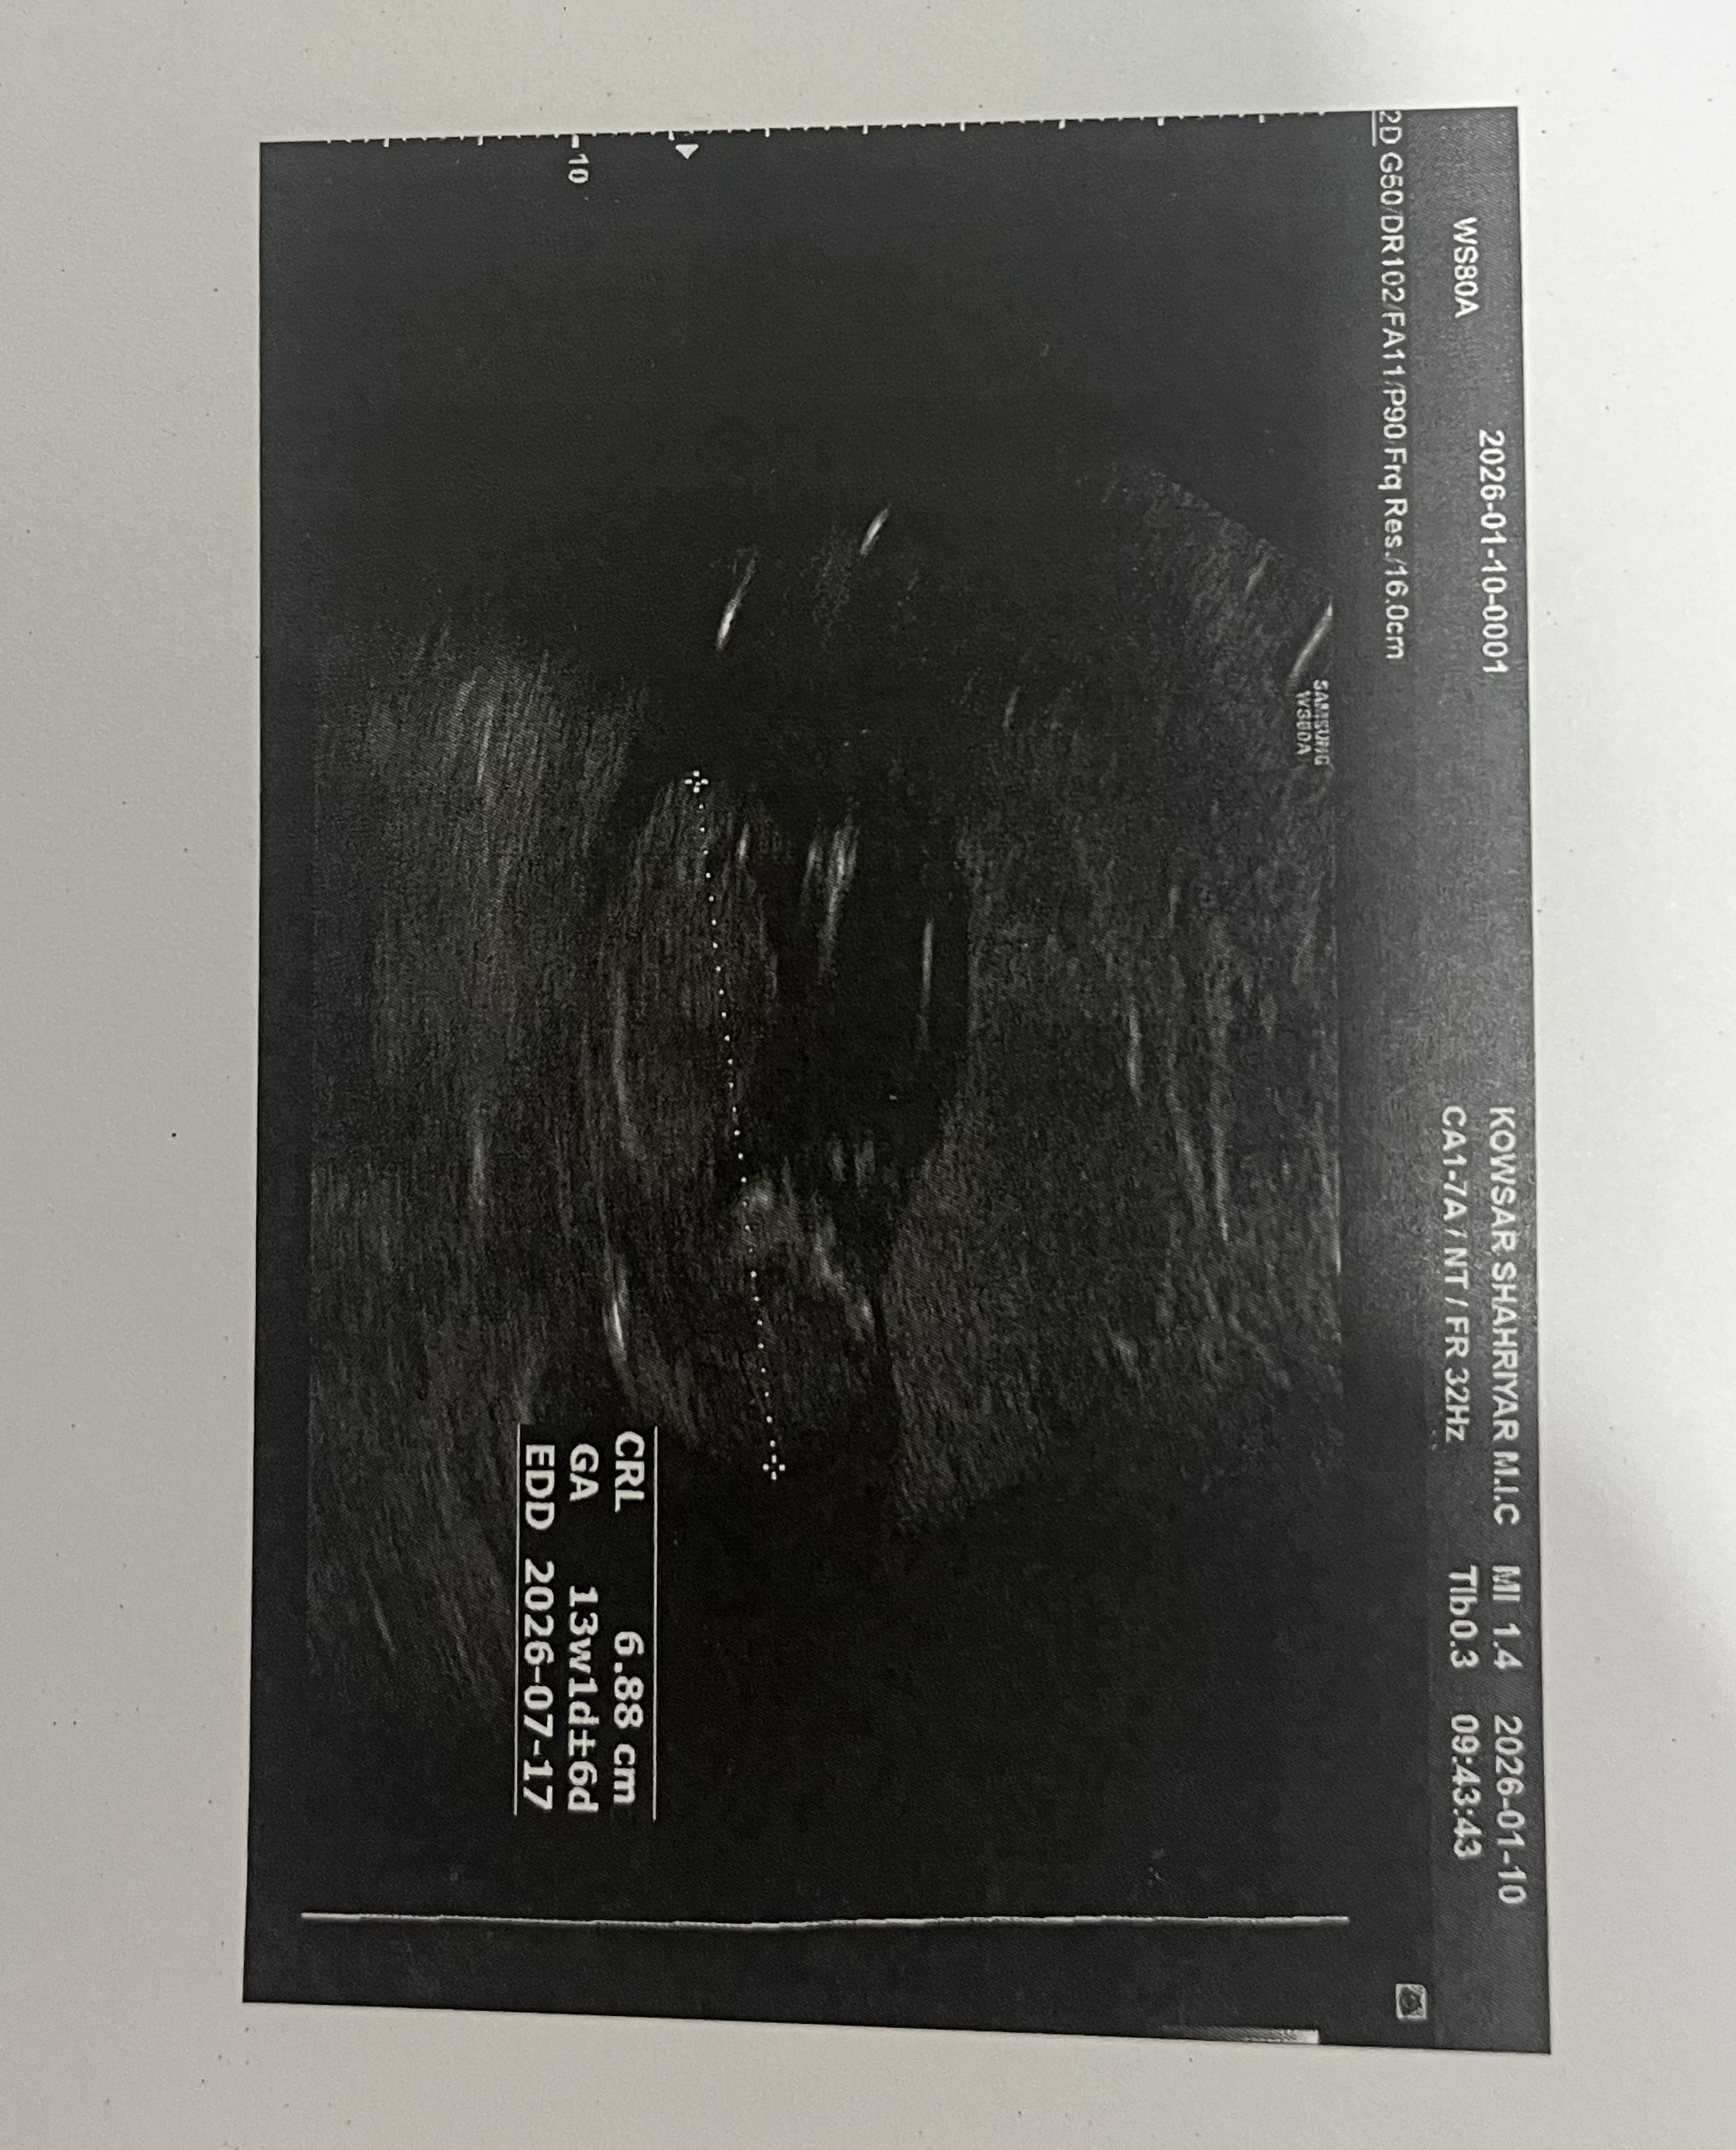

مگه تو ان تی نمیگن تا حدودی من 15 روز دیگه نوبت ان تی دارم